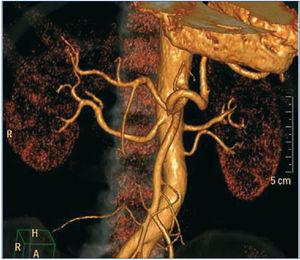

La DNSR se realizó sin complicaciones (figura 2); se decidió no tratar la arteria polar inferior del riñón izquierdo, ya que no alcanzaba el diámetro menor exigido, apreciándose únicamente en el control radiológico inmediato posterior espasmo de la arteria renal izquierda (figura 3), que se solventó con la inyección de nitroglicerina, y por lo que decidimos iniciar antiagregación con triflusal.

Figura 3. Espasmo de la arteria renal izquierda tras procedimiento